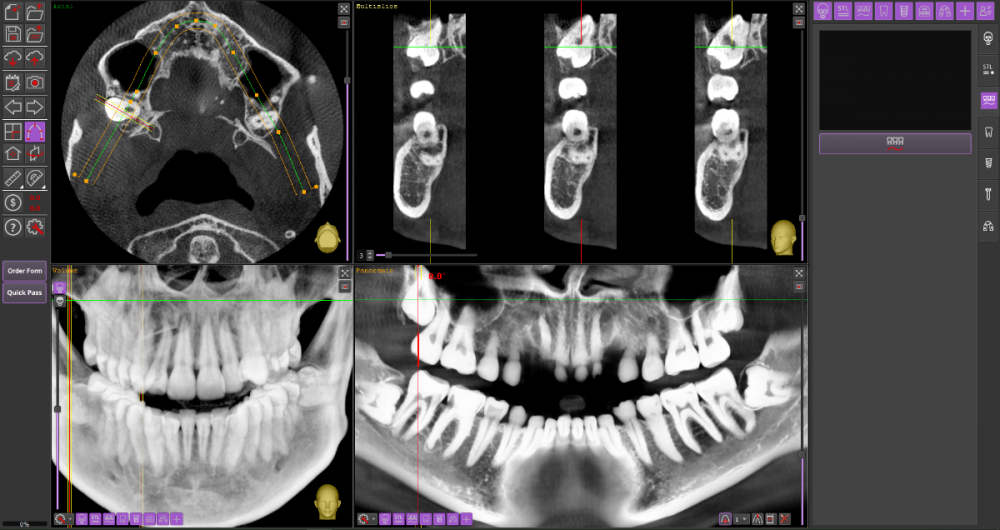

Прошу Вашего совета по поводу удаления восьмых зубов.

Из жалоб есть непродолжительная ноющая боль в правой нижней челюсти, не связанная с внешними раздражителями.

1. Необходимо ли удаление зубов мудрости?

2. Возможно ли удаление амбулаторно, без общего наркоза?

3. Нет ли риска для семёрок при удалении.

28_1.thumb.png.19ca43126a8beb1bc956730f3bde22dd.png

28_2.thumb.png.12dc5849ff22079dde8e4e3d22010bf2.png

Виновником боли в н.ч. справа может быть, например зуб 46, не только 48.

1. Удаление 8-х зубов скорее всего необходимо

2. Удаление амбулаторно вполне возможно. Общая анестезия (наркоз) совершенно необязательна, местной анестезии достаточно.

3. Несчастные случаи бывают, но крайне редко.